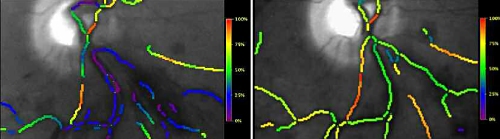

Results: The venular SO2 was 59±6 % in healthy fellow eyes (mean±SD; n=5), 60±12 % in

non-occluded areas of RVO eyes (n=4), 39±23 % before laser in occluded venules (n=5) and 56±4 % in occluded venules following laser treatment (n=5). Before laser the occluded venules have a significantly lower SO2 than healthy eyes or nonoccluded

areas of RVO eyes (p<0.05) and the SO2 was normalized by laser treatment. In the 4 eyes measured both before

and after laser treatment the SO2 rose from 38±26 % to 57±4 % (p= 0.24, paired t-test). The figure shows a pseudocolor SO2 map before and after laser treatment.